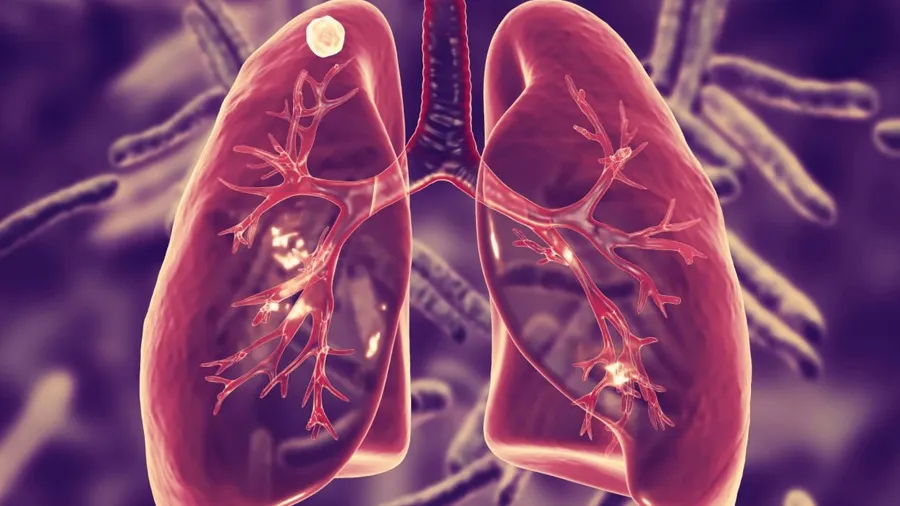

પાલ્મોનોલૉજિસ્ટ ડૉક્ટર લેંસલોટ પિન્ટોએ ચર્ચા દરમિયાન કહ્યું કે, લગભગ 40 ટકા લોકોમાં TBના લક્ષણ હોય છે. આ 40 ટકા લોકોમાં 5 ટકા લોકોને આ બીમારી પોતાના શિકાર બનાવી લે છે. તેમણે આગળ કહ્યું કે, TBને લઈને લોકો માનવા માગતા નથી કે તેઓ આ બીમારીની ઝપેટમાં છે. આ કારણે તેમની તપાસમાં મોડું થઈ જાય છે અને તેઓ TBના શિકાર થઈ જાય છે. જો તમને થોડા દિવસોથી ખાંસી હોય તો ડૉક્ટરને દેખાડવું જોઈએ.

જો ડૉક્ટરને દેખાડ્યા બાદ પણ ખાંસીની પરેશાની છે ડૉક્ટરની સલાહ પર TBની તપાસ કરાવવી જોઈએ. TBની તપાસની રીત પણ ખૂબ બદલાઈ ગઈ છે. પહેલા માઈક્રોસ્કોપથી જ્યારે તપાસ થતી તો તેમાં 40 ટકા TB ઉત્પન્ન કરનારા કિટાણુઓની જાણકારી મળી શકતી નહોતી, પરંતુ હવે નવી ટેક્નિકના માધ્યમથી થઈ રહેલી તપાસમાં ઘણું બધુ સ્પષ્ટ થઈ જાય છે. એ ખોટી ધારણાં બની ચૂકી છે કે TB માત્ર સમાજના ગરીબ વર્ગોથી આવનારા લોકોને જ ઝપેટમાં લે છે, જ્યારે એવું કશું જ નથી.

ડૉ. પિન્ટોએ આગળ કહ્યું કે, જો તમે ડાયાબિટિશના શિકાર છો તો તમને TB થવાનું જોખમ પણ વધારે છે. જો તમે સિગારેટ પીવ છો તો પણ તમને આ બીમારી ઝપેટમાં લઈ શકે છે. તેની સાથે જ જો તમને લીવર કે કિડની સાથે જોડાયેલી બીમારી છે તો પણ TBનો શિકાર સરળતાથી થઈ શકો છે. ચર્ચા દરમિયાન એક્સપર્ટ પેનલમાં સામેલ હેલ્થ સ્ટ્રેટેજિસના વરિષ્ઠ ડિરેક્ટર રમણ શંકરે પણ ઘણી મહત્ત્વની વાતો કહી.

TBની અસર માત્ર દર્દી જ નહીં, પરંતુ તેની સાથે જોડાયેલા લોકો પર પણ પડે છે. તેને આ ખતરનાક બીમારીથી બહાર નીકળવામાં લગભગ 4 વર્ષનો સમય લાગી ગયો. તેને આ બીમારીના કારણે ફેફસા પણ ગુમાવવા પડ્યા. જો કોઈને TB જેવી ગંભીર બીમારી થાય છે તો તેની સમય પર સારવાર ખૂબ જરૂરી છે. જો ઓળખમાં મોડું થાય છે તો TBની બીમારી ઘણી હદ સુધી બગડી જાય છે. તેના ઘણા સ્ટેજ હોય છે. થોડી ગંભીર કન્ડિશનમાં દવાઓની અસર પણ ઓછી થઈ જાય છે અને TB ગંભીર રૂપ લઈ લે છે તો દર્દીનું બચવું મુશ્કેલ થઈ જાય છે.